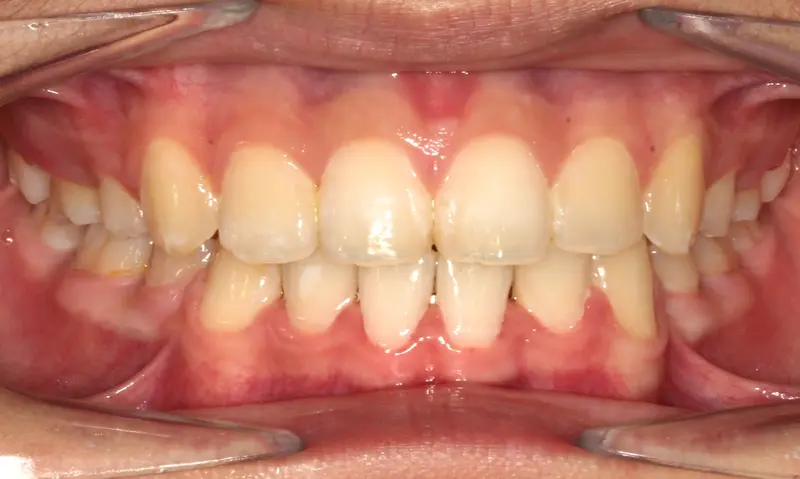

The Diagnosis

Bimaxillary protrusion (teeth flaring forward) causing lip incompetence. The patient struggled to close his lips comfortably, straining the chin muscle (mentalis).

The Engineering

A strategic extraction plan (4 premolars) allowed us to retract the front teeth. Note the dramatic improvement in chin projection and facial balance. The extractions did not flatten the face; they harmonized it.